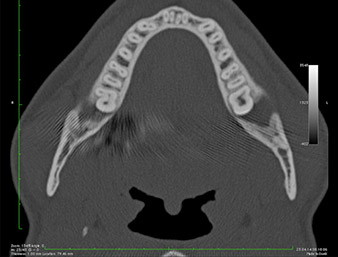

Ya en la ortopantomografía, se constató que había un resto radicular de la región 38 muy cerca del nervio alveolar inferior (figura 1). La raíz se había fracturado durante la osteotomía, pero el primer odontólogo que había tratado al paciente no había extraído esta debido a la presencia de dolor durante la operación.

Ortopantomografía

Imagen 1: Ortopantomografía 6 meses después de la osteotomía del diente 38: el resto radicular se encontraba cerca del nervio alveolar inferior.

En la imagen en 3D (tomografía volumétrica digital) se constató que el resto radicular se encontraba muy desplazado en sentido distocaudal en la transición situada entre la porción horizontal y la ascendente del maxilar inferior (figura 2).

TVD transversal

Imagen 2: Representación de una TVD transversal del resto radicular en el espacio retromolar.

La anamnesis del paciente era favorable (no fumador, 26 años) para garantizar el éxito de la aplicación. Como la ortopantomografía mostró que el resto radicular se encontraba muy cerca del nervio alveolar inferior, se realizó también una tomografía volumétrica digital (6).